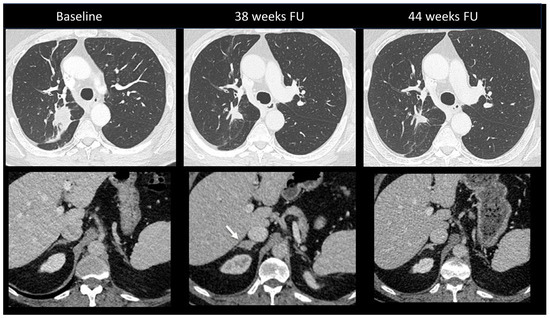

2.2.2. Sarcoidosis-Like Reaction

- Gkiozos, I.; Kopitopoulou, A.; Kalkanis, A.; Vamvakaris, I.N.; Judson, M.A.; Syrigos, K.N. Sarcoidosis-Like Reactions Induced by Checkpoint Inhibitors. J. Thorac. Oncol. 2018, 13, 1076–1082. [Google Scholar] [CrossRef] [PubMed]

| Other toxicities | Sarcoidosis-like Reaction | Enlarged hilar and mediastinal lymph nodes +/− bilateral perylimphatic (mainly scissural) micronodules | Bilateral and symmetrical | Lymph node metastasis disease Lymphangitis |